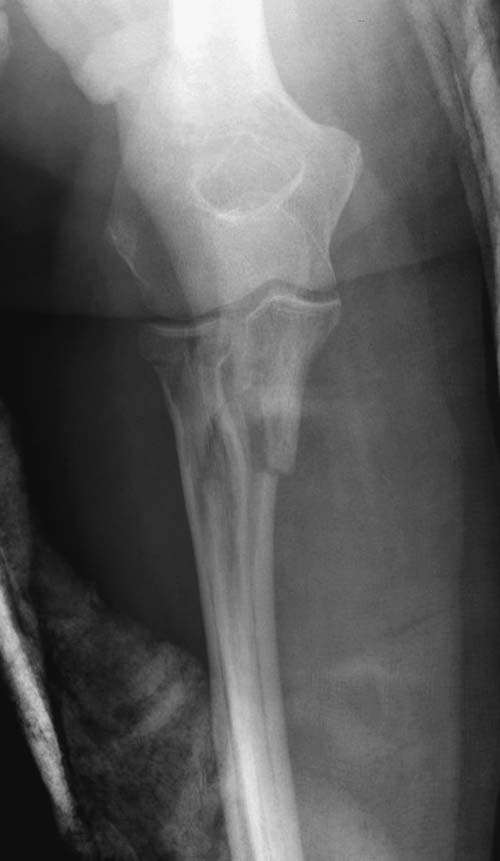

Судя по 3-Д КТ, перелом - много оскольчатый, но без смещения.

Один снимок всего? Может КТ-срезы какие-нибудь есть, R-снимки без гипса фас/профиль? По этому снимку вроде бы и нет вдавленного перелома. Суставная поверхность расколота - это да, но импрессии не увидел. Мы бы попытались сохранить головку.

Синтезировать, или вообще не трогать. А 3D картинки дают мало информации. Лучше представляйте срезы в 3-х плоскостях.

На представленных снимках есть смещение суставной поверхности. Принцип лечения внутрисуставных переломов - восстановление суставной поверхности. У нас есть опыт восстановления таких переломов микровинтами. Удачи!

Для выработки показаний достаточным бывают стандартные снимки, но иногда требуется косая рентгенограмма по Coyle. И для подтверждения смещений и оценки внутрисуставных фрагментов рекомендуется КТ, а 3D снимки показывают только поверхность, т.е. получается общая картина. МРТ дает возможность оценить состоянии связок.